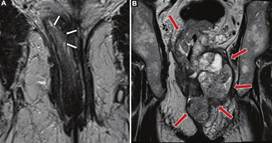

Invasión vascular extramural

La invasión vascular extramural (IVEM) hace referencia a la presencia de células tumorales dentro de estructuras vasculares más allá de la muscular propia rectal3, siendo la RM el único método por imágenes comprobado con la capacidad de detectarla (Figs. 18 y 19)8,15. Se estima que está presente en hasta la mitad de los casos de cáncer rectal y es un factor de riesgo independiente de recurrencia local y a distancia, y un indicador de mal pronóstico9,16,17. La figura 18 expone la diferente clasificación de IVEM y en la figura 19 se exponen algunos ejemplos.